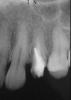

igorstom Опубликовано 13 августа, 2008 Поделиться Опубликовано 13 августа, 2008 Сегодня на приёме была пациентка по поводу замены на 24 зубе комбинированной коронки на металлокерамику. Десна в области проекции верхушки и окружающие ткани без особенностей. Подвижности патологической нет, перкуссия безболезненная. Снял "комбинашку" и увидел анкер, вокруг пломбы вторичный кариес. Принял решение удалить анкер и сделать ВКВ. Рентгеновский снимок обескуражил - перфорация? Скорее всего. Какие будут предложения? Удалять зуб не хотелось бы - моя знакомая, и при любом раскладе в суд подавать не будет. Прорутом не работал, да и нет его. Спасибо заранее за ответы. Чуть не забыл - зуб под коронкой простоял около 5-6 лет. Ни разу не беспокоил. Ссылка на комментарий

Большой Зеленый Опубликовано 13 августа, 2008 Поделиться Опубликовано 13 августа, 2008 Да нету там никакой перфы ! Если бы была то были бы и изменения на снимке ,а там все ровно .Тем более 5 лет не беспокоил .И в каналах материал прослеживается. Если вы анкер добудете ,то честь вам и хвала .Только не забывайте главный принцип. НЕ НАВРЕДИ! Я возражу Аннде . Я против перелечивания . Ни к чему. Ссылка на комментарий

Bier Опубликовано 13 августа, 2008 Поделиться Опубликовано 13 августа, 2008 между прочим в месте возможной перфы есть изменения на снимке, я предлагаю удаление+ одномоментная имплантация с одномоментной нагрузкой временной коронкой. Ссылка на комментарий

DENT37 Опубликовано 14 августа, 2008 Поделиться Опубликовано 14 августа, 2008 Немного изменить ангуляцию тубуса. Здесь явное укорочение зубов-так сделайте снимок чтобы понять форму корня. Ссылка на комментарий

Зубодер Опубликовано 14 августа, 2008 Поделиться Опубликовано 14 августа, 2008 Там всё ровно??? Мдя.+1 я бы даже сказал что там довольно таки криво и думаю перф есть Ссылка на комментарий

Нск Опубликовано 14 августа, 2008 Поделиться Опубликовано 14 августа, 2008 Кривенько стоящий анкер ни есть повод к удалению, даже при наличии такой периодонтальной щели. Убрать анкер, пощупать стенку локатором, залить её прорутом, если пищит, СВШ буржуйский конусный, коронка. Ссылка на комментарий